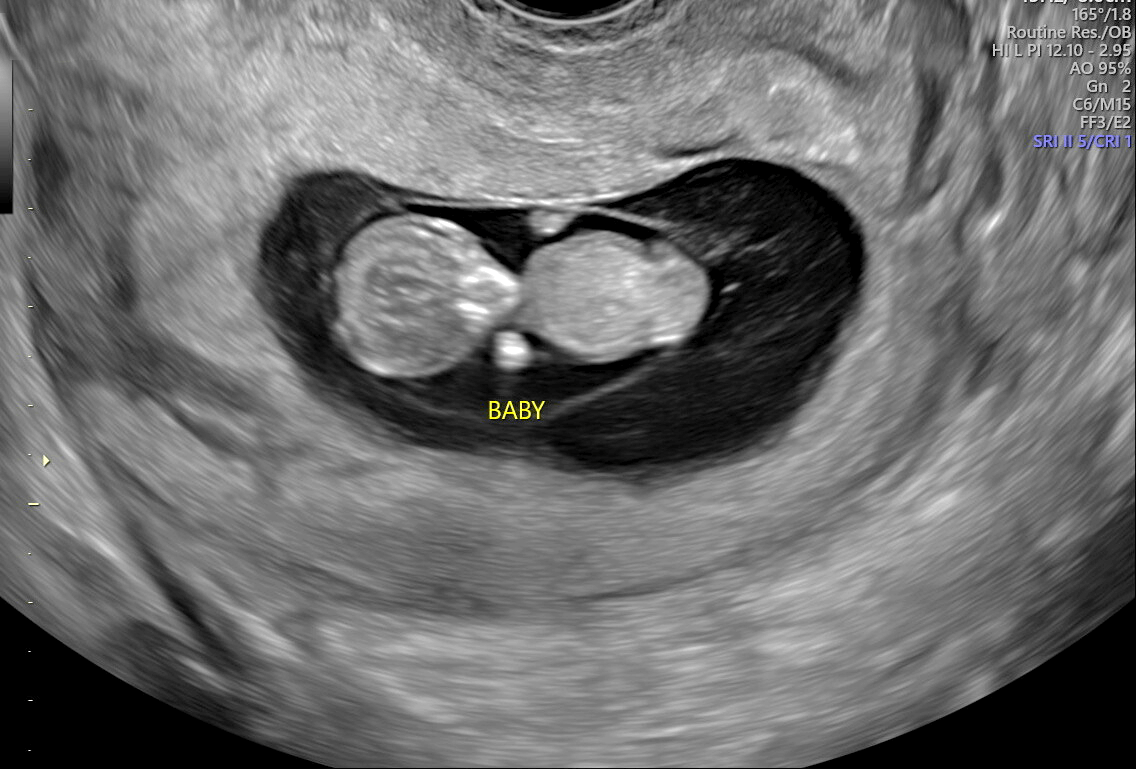

10-week ultrasound (size of a grape)

He was wiggling around so much in this session! It was so much fun to see little fingers and toes developing!